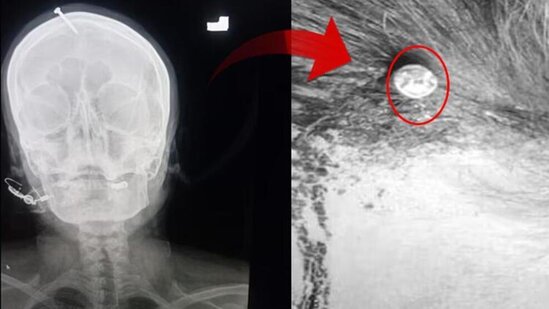

ŞOK HADİSƏ: Oğlu olsun deyə başına mismar vurdular - FOTO

Pakistanda hamilə qadın başında 5 sm uzunluğunda yara ilə xəstəxanaya yerləşdirilib. Əvvəlcə qəza kimi görünən hadisənin əsl səbəbi hətta həkimləri belə, şoka salıb.

Sonxeber.az xarici mətbuata istinadən xəbər verir ki, 3 qızı olan ana, bətnindəki körpənin də qız olduğunu öyrəndikdən sonra ərinin ondan ayrılmaq təhdidləri qarşısında aciz qalıb və bu cür ağlasığmaz üsula əl atıb.

Belə ki, şəxsiyyəti açıqlanmayan qadın ərinin hədələrindən sonra özünə "şəfaçı" tapıb. Qondarma "şəfaçı" çarəsiz qadına oğlunun olması üçün başına mismar vurmalı olduğunu deyib.

Həkimlər qadının başındakı mismarı əməliyyatla çıxarıblar. Sosial şəbəkələrdə sürətlə yayılan "X-ray" görüntülərindən sonra polis hər yerdə "şəfa verən qadını" axtarır.